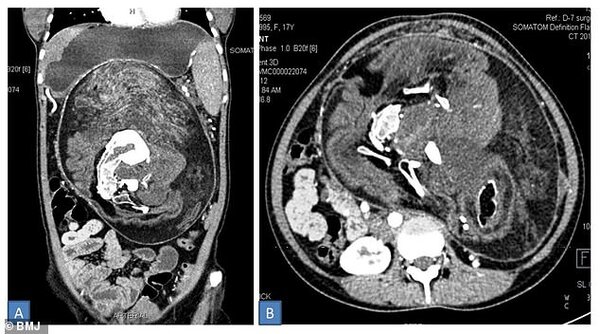

Медики обнаружили в животе пациентки странную опухоль. Томография показала наличие разных тканей. В том числе кости - в частности, позвонки, ребра и «длинные кости», согласно отчету врачей. А также волосы, несколько зубов и «структуры, напоминающие конечности».

Пациентка из Индии стала самой взрослой в истории с таким диагнозом. Она единственная в мире женщина, которая прожила 17 лет с близнецом внутри. Все эти годы он находился в забрюшинном пространстве (от диафрагмы до малого таза). У близнецов было общее кровоснабжение. Размер неразвитого плода составил 30 × 16 × 10 см.